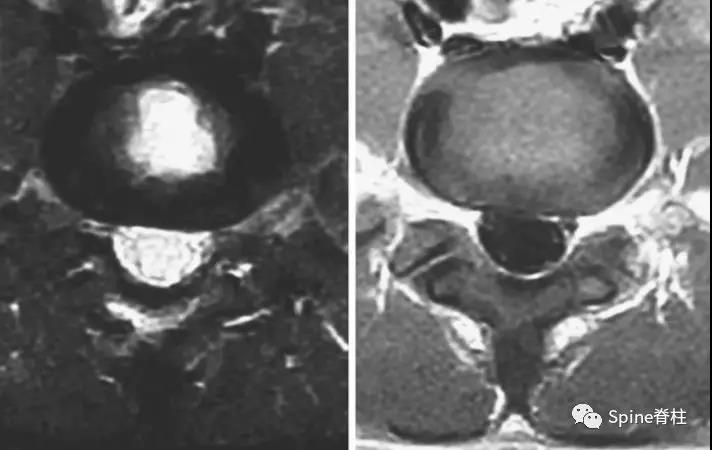

2003年发表在Am J Sports Med杂志(IF=6.20)上的病例报道,很好的阐述了峡部裂和椎弓根裂的变化。描述一个17岁的棒球运动员,运动后腰痛1月余,随访的辅助检查提示相同椎体水平出现的3个连续性应力性骨折:第一次为左侧峡部,第二次为右侧椎弓根,第三次为右侧峡部。

图:6个月复查可见右侧椎弓根裂已愈合(单箭头),但出现右侧峡部裂(双箭头)